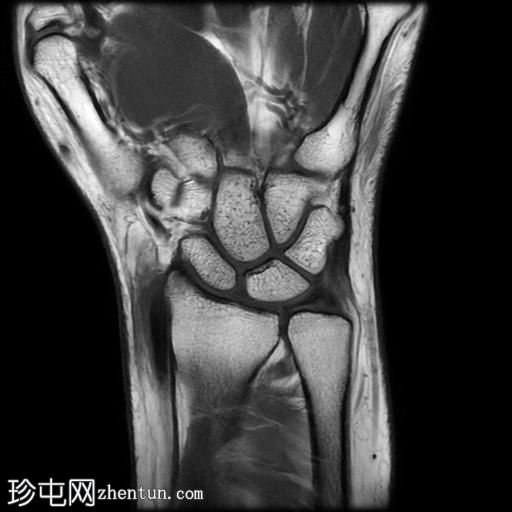

De Quervain腱鞘炎MRI

MRI

冠状面PD值

脂肪饱和度

冠状面

T2

T1

矢状面

PD值

轴向PD值

轴向

MRI显示腕部第一背侧肌腱(拇长展肌和拇短伸肌)增厚,并伴有异常增厚的实质内液体信号。腱鞘内液体增多。

尺侧腕伸肌腱可见异常线性实质内液体信号增多,与板状间质撕裂相关。

病例讨论

MRI表现和临床表现提示De Quervain腱鞘炎。